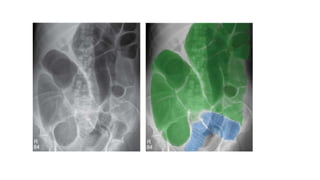

Radiological signs :

1. dilatation >3cm - for quick

comparison the adult vertebral

body measures 4cm.

2. central location

3. valvulae conniventes-

musical folds of the SI. Thin ,

closely spaced and classically

seen as a continuous thin line

across the entire width of the

bowel .